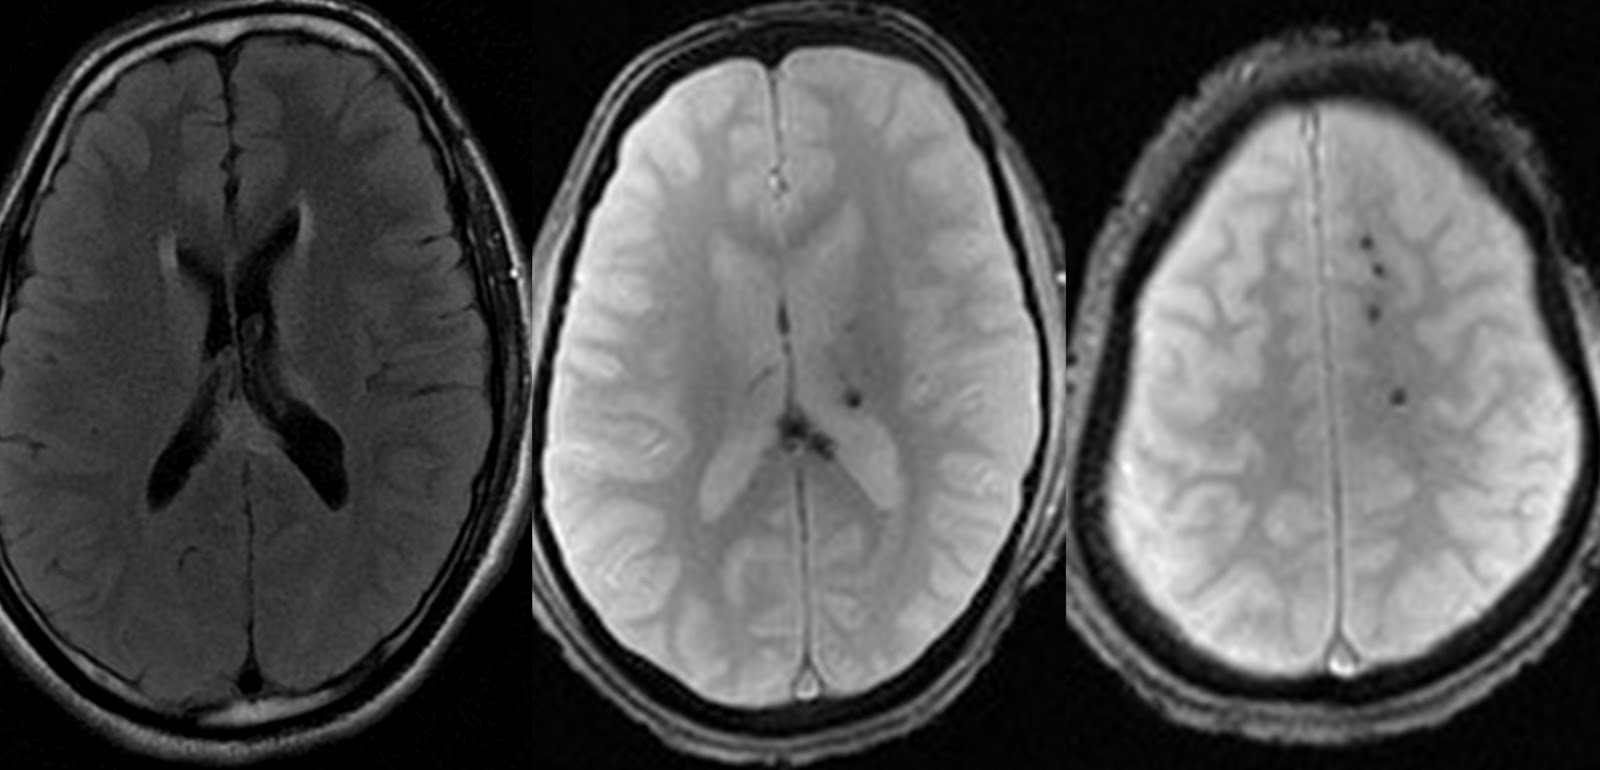

More recently the term has been expanded to include any rapid gradient-echo or spin-echo sequence in which k-space is traversed in one or a small number of excitations.The widely used magnetization-prepared rapid gradient-echo (MPRAGE) sequence makes enhancing lesions and blood vessels appear bright after gadolinium administration. In-slice signal loss caused by background macroscopic susceptibility gradients is mitigated by combining three successive gradient-echo images whose slice refocus gradients are successively incremented.Rapid gradient-echo sequences consist of a single RF excitation, imaging gradients, and acquisition, as shown in Fig. The resulting T1-weighted images were .Gradient echo sequences form the basis for an essential group of imaging methods that find widespread use in clinical practice, particularly when fast imaging is important, as for example in cardiac MRI or contrast-enhanced MR angiography.1 INTRODUCTION.02 Department of Radiological Sciences David Geffen School of Medicine at UCLA.